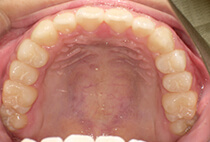

40代女性の患者さま。

グラグラする歯と乱れた歯並びが気になりご来院されました。

「見た目も気になるし、このまま歯が抜けるかも…」そんな不安を抱えていらっしゃいました。

治療は3ステップで進めました。

矯正後は、かぶせ物の治療もあわせて行い、「しっかり噛めて、見た目も自然で美しく」を達成できました。

しっかり噛めるようになったことで頬のコケ間や口元のゆるみが改善され若々しく引き締まった印象になりました。

そして何より、治療終了から15年後も歯ぐき・歯並びともに安定し、健康的で美しいお口元をキープされています。

グラグラする歯と乱れた歯並びが気になる

叢生、重度歯周病

40代女性

矯正治療1年、歯周治療3ヶ月

唇側矯正、審美治療、歯周病治療

矯正:955,900円+毎月調整量:6,050円

歯ぐきの炎症をしっかり改善(歯周病治療)してから、装置セット。

歯並びと噛み合わせを整える(表側矯正・1年間)。

見た目と機能の仕上げ(審美的なかぶせ物)。

治療終了から15年後も歯ぐき・歯並びともに安定し、健康的で美しいお口元をキープされています。